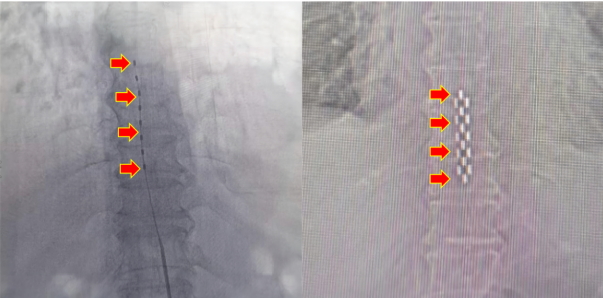

临时刺激电极(左) VS 永久刺激电极(右)

最初神经外科予以临时脊髓电刺激治疗,患者左足血供明显好转,创面加速愈合、结痂。在临时治疗效果显著的情况下,予以二期手术,植入永久刺激器。术后患者疼痛明显缓解,缺血情况显著好转,成功保肢。日前,患者恢复顺利,患者及家属对治疗效果表示满意。